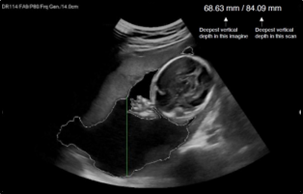

Estimating gestational age and predicting preterm birth, aneuploidy, and asymptomatic short cervical length have been investigated using machine learning algorithms (Safiullina et al., 2023). An effective system was developed for predicting fetal brain abnormality. A recent systematic review demonstrated that a model for the prediction of prematurity using the support vector machine technique performed best among 31 studies analyzed, with an accuracy of 95.7% (Bertini et al., 2022). Deep learning-based automatic measurement programs for parameters indicating the progression of labor (e.g., the angle of progression) are currently applied (Lu et al., 2022). AI-based programs have advantages in terms of obtaining more objective results and may be helpful for parameters that are clinically important but may have errors between measures. For example, measurements of amniotic fluid are susceptible to errors between measurements, which can affect treatment decisions, and AI-based programs that can automatically measure these items are being developed (Figure 2), (Kim et al., 2022). A recently published paper reported that an automated method based on deep learning was very useful for measuring amniotic fluid (Cho et al., 2021). In addition, AI-based programs can be helpful for measurements that require evaluators to be fully trained and experienced, such as nuchal translucency, and these techniques may be combined with a robot arm that performs the scanning to automatically extract standardized fetal imaging views (Nie et al., 2017).

Figure 2: Artificial intelligence–based automatic amniotic fluid measurement program using deep learning. The amniotic fluid part is automatically extracted from the given image and the deepest vertical depth of the amniotic fluid part; that is, the amniotic fluid index is automatically calculated (Kim et al., 2022).